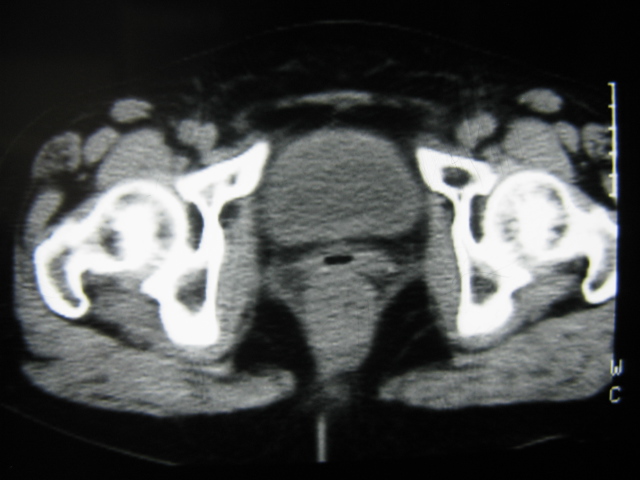

患者,女,64岁,2002年诊断为宫颈癌,当时只做过放,化疗。现在诊断:(1)宫颈癌。(2)直肠癌。请同道们讨论,探讨。另外肠壁为啥密度这么高,ct值约112hu。患者没有做过增强和造影。

高密度的不是肠管影,是肠管内的粪便影

患者直肠病变,排便不畅,粪便硬结造成,更高密度如钡灌肠者都可出现

硬结粪便能有如此高密度影?

我也碰到过几例,最离奇的一例是全结肠呈造影样高密度,患者直肠癌(首次发现),以往没有吃药,只有约半年时间长的胃纳差,排便不畅(据患者说每次大便只能拉出少许黄水)

不一定有意义,可清洁灌肠后复查